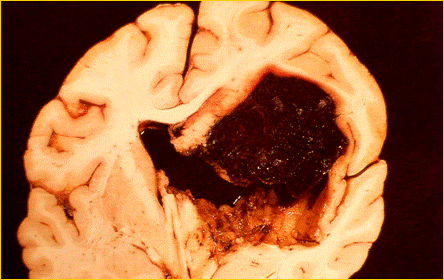

REPERTO ANATOMICO DI MASSIVA EMORRAGIA CEREBRALE

Le patologie che possono portare alla morte cerebrale sono l'emorragia cerebrale da rottura di un vaso intracranico, i traumi cranici ( incidenti stradali, ferite da proiettile ), le neoplasie cerebrali primitive.

EMATOMA SUBDURALE FERITA DA PROIETTILE